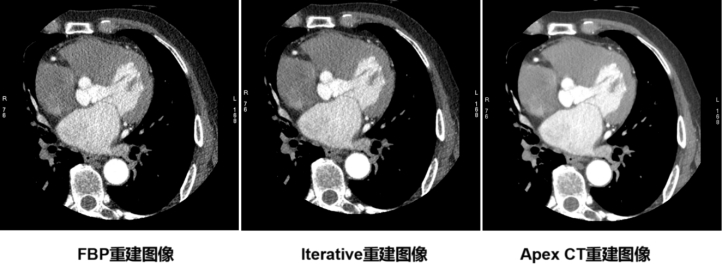

经过半个多月的安装、调试、培训等环节,GE全球首款通过美国FDA认证的人工智能CT系统APEX CT于4月20日在安徽医科大学第一附属医院绩溪路院区正式投入使用。APEX CT是业界首个获得美国FDA认证的一款基于深度学习重建算法的256排512层能人工智能CT系统。与其他CT不同,APEX CT聚焦目前对人类健康威胁最大的心脑血管疾病和肿瘤疾病,创新性突破以往十年来CT影像重建算法的桎梏,拥有极“清”全身血管、极“早”肿瘤筛查、极“低”剂量真理图像的特点和优势。它具备业内领先的硬件平台,可以做到冠脉、全身血管的超早期肿瘤一站式扫描,且每一次扫描都能获得以往CT设备无法比拟的高清图像质量,最大程度的保留了图像的真实纹理、解剖结构和病理细节,实现了低剂量、低噪声和真实图像纹理的三位一体。APEX搭载创新的CT迭代重建算法,借助深度神经网络训练开发出全新人工智能CT图像处理技术,并通过持续学习高清真实影像数据,获得更高质量的图像,助力放射科医生对疾病疾病进行精准诊断。

更加先进的AI算法,实现超低剂量成像、超低对比剂成像,减轻对比剂副作用的发生。Apex CT具有一键去除血管内对比剂的功能“黑血技术”,从而去除对比剂对血管壁的影响,清晰显示血管壁的情况

基于AI的算法大大降低低剂量下图像的噪声,为精细显示病灶的显示提供帮助,并且大大减少对比剂的用量